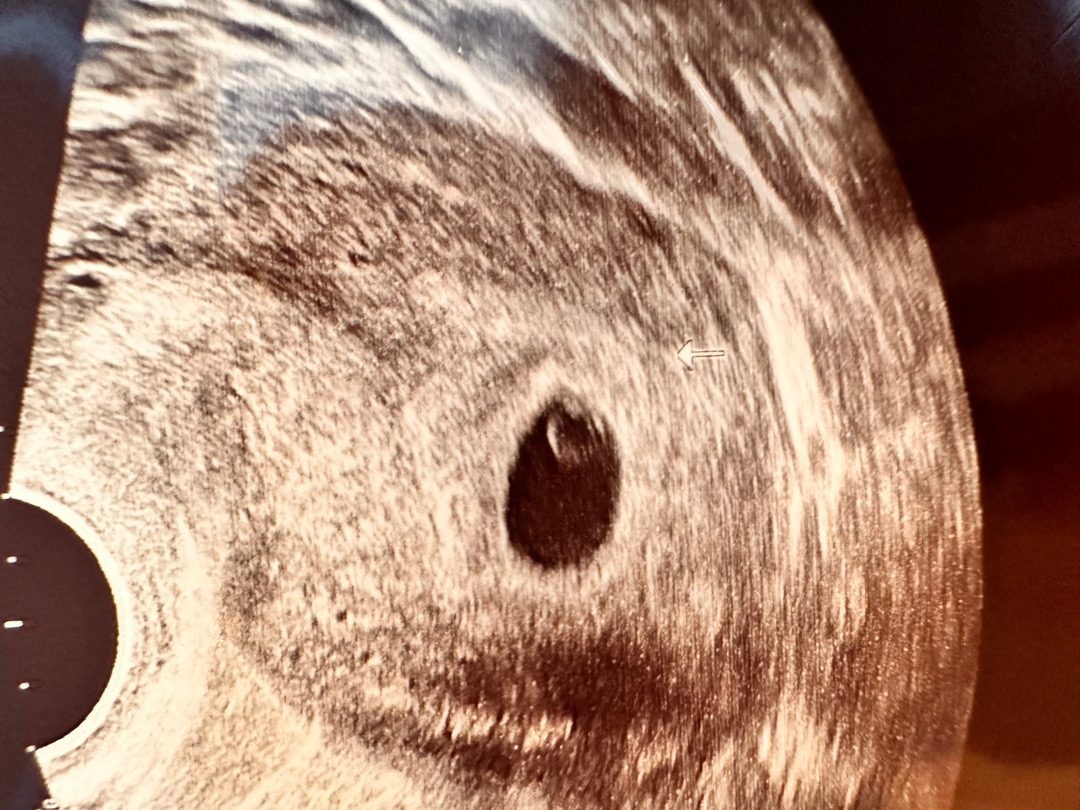

오늘 심소들으러 갔는데 안들렸어요 ㅠㅠ

후우~ 아기도 보긴 했는데 심장이 뛰는 반짝임은 봤는데 6주 1일이에요 ㅠㅠ 너무 작아서 소리가 안들렸는데 원장님이 저보고 체지방이 있으면 안들린다고 살빼래요 ㅠㅠ 비만이어도 심소 안들리는건가요?? ㅠㅠ